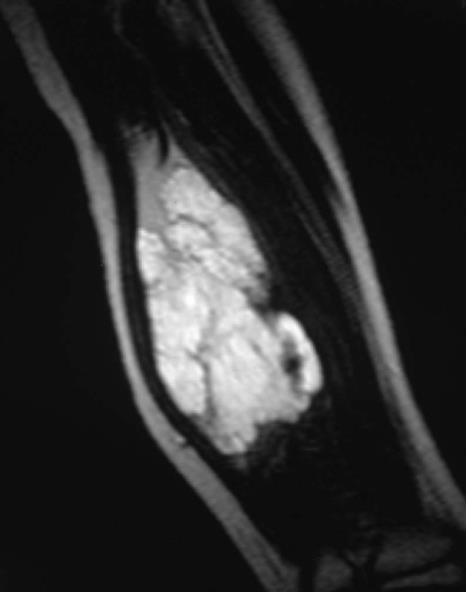

儿童静脉畸形的分类和硬化影响[1] ![]() III 和IV型静脉畸形的栓塞比较 I 和 II型静脉畸形栓塞高度危险

Volkmann’s Contracture(福克曼缺血性挛缩)是由于肢体严重缺血,造成肌肉坏死或挛缩,又因神经缺血和瘢痕压迫,常有神经部分瘫痪,致肢体严重残废。